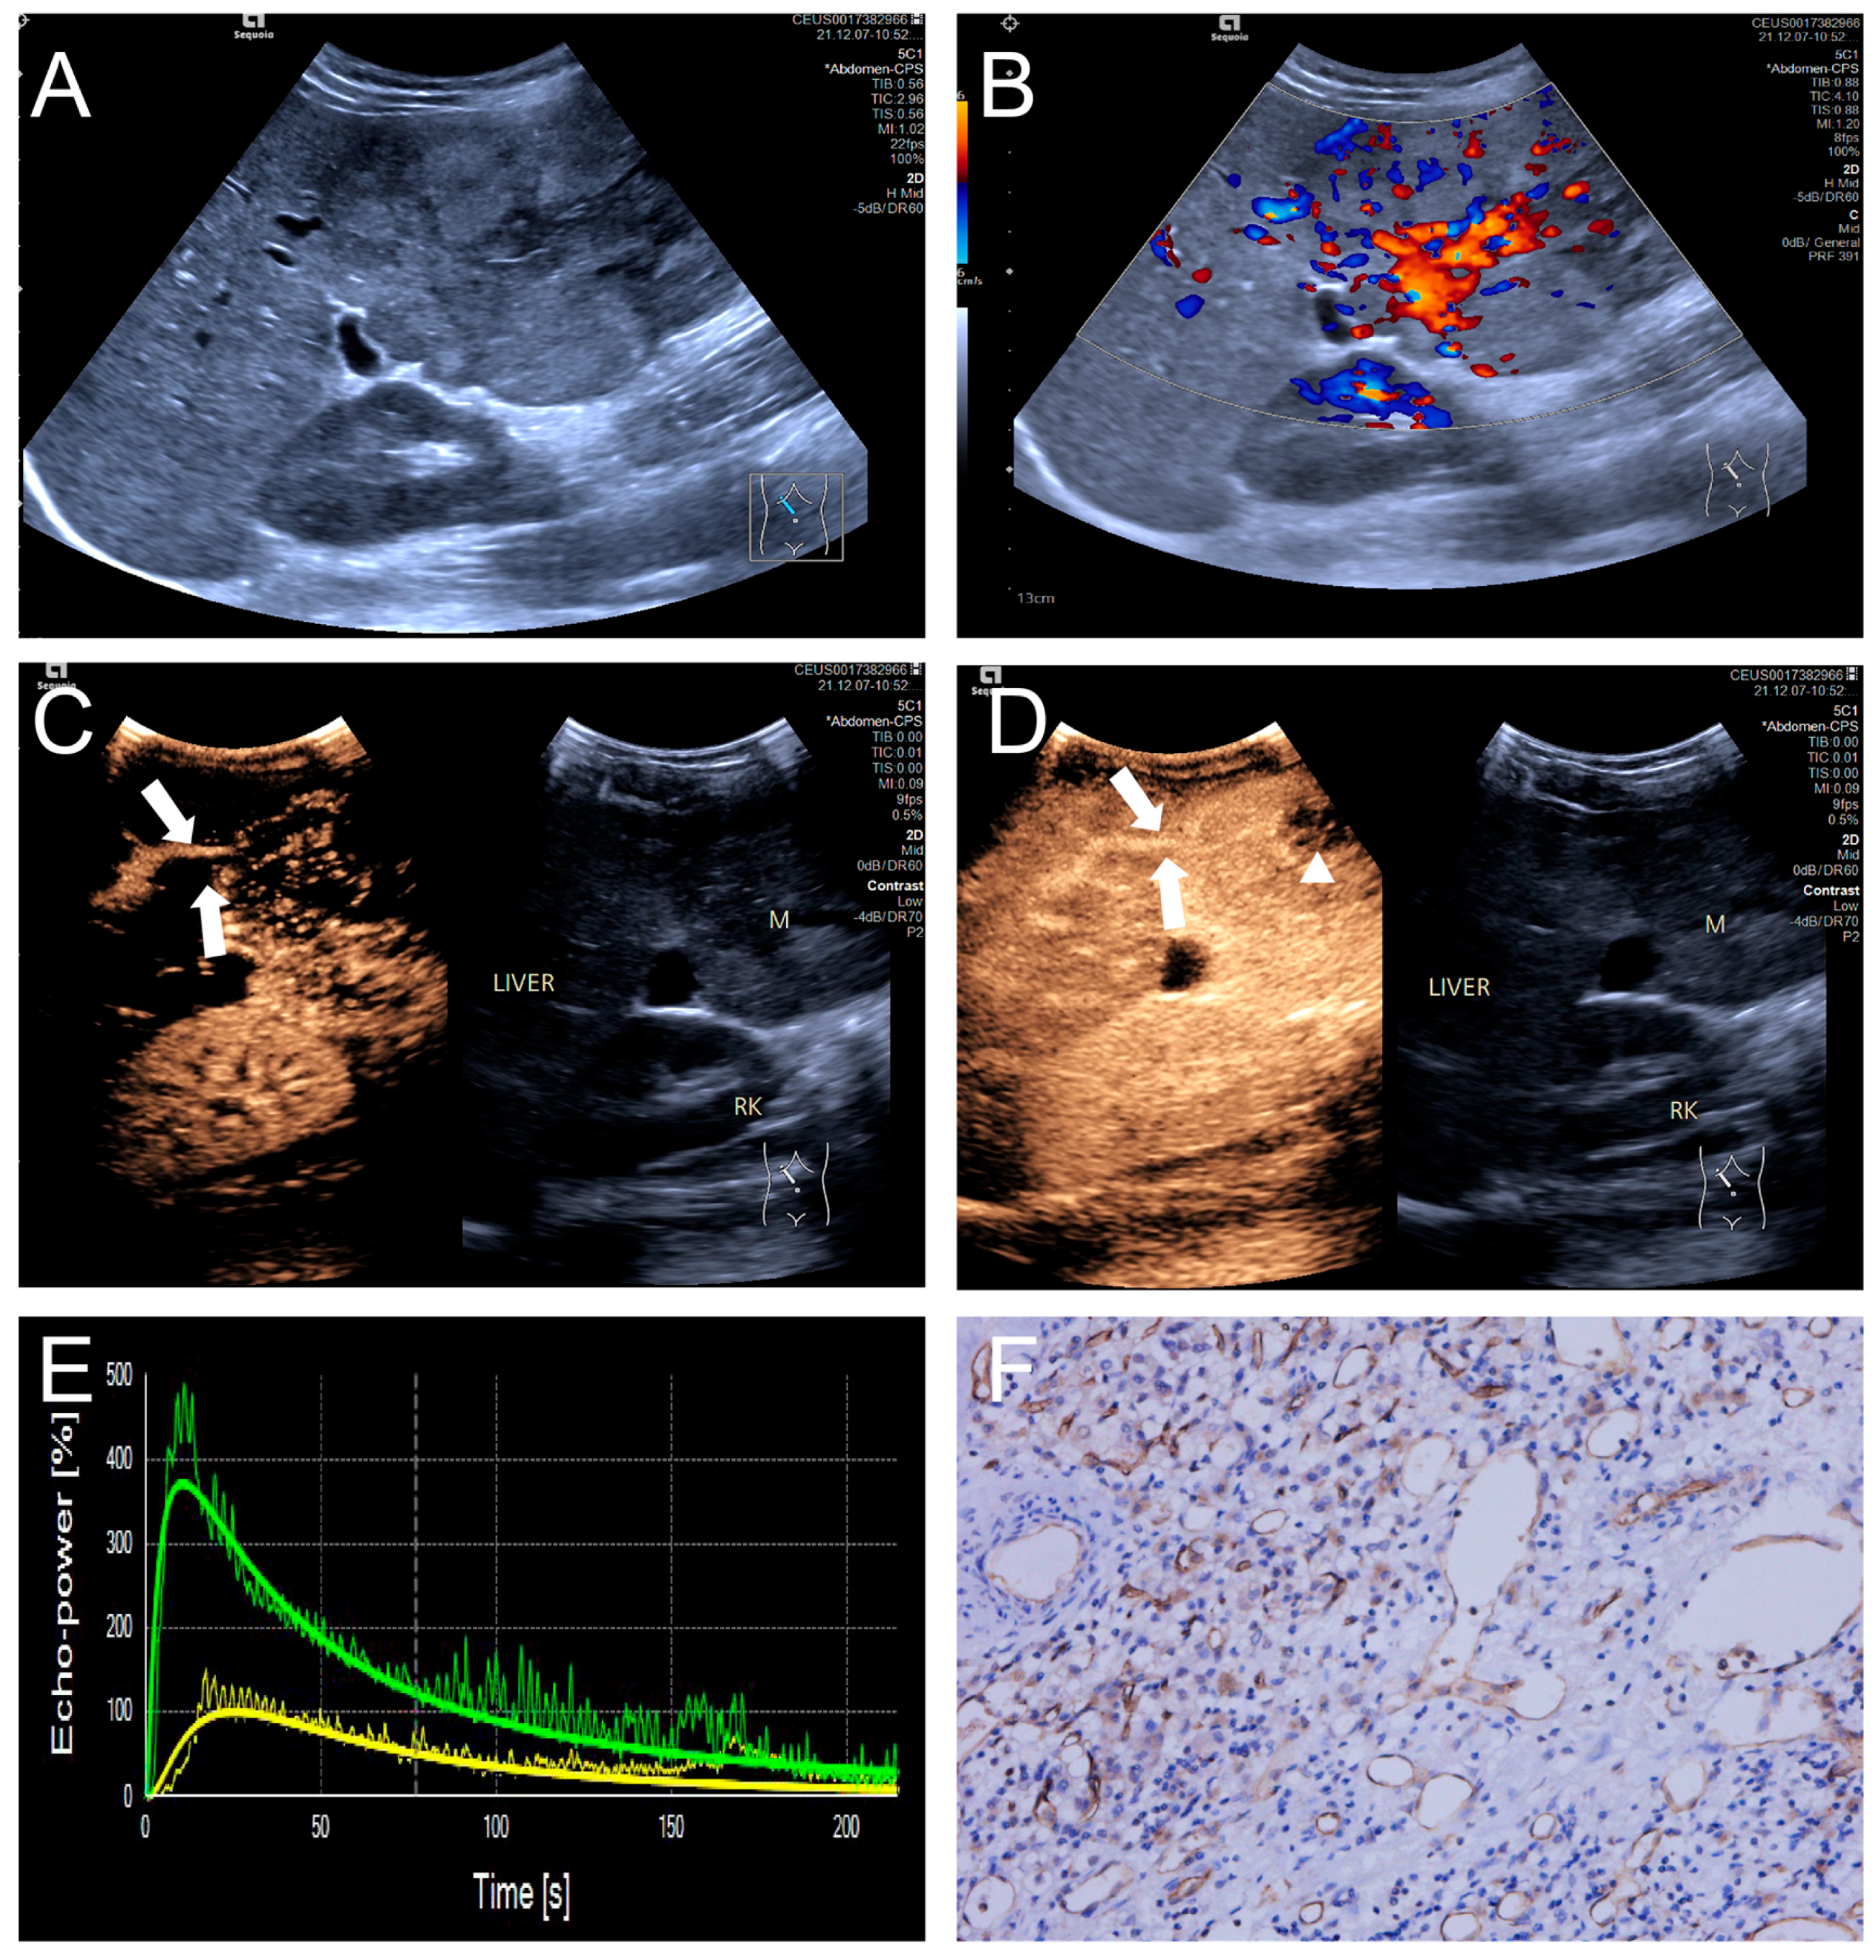

Figure 3.

(A–F) A male patient aged 4 years and 4 months with HB and low MVD. (A) The imaging revealed a well-defined mass with clear margins and hyperechoic echogenicity in the right hepatic lobe; (B) The tumor’s color Doppler flow imaging revealed distinct blood flow patterns and Adler grade I blood flow; (C,D) The CEUS exhibited uniform internal enhancement from periphery to center without any peripheral penetrating vessels; (E) TIC curves showed contrast enhancement of the lesion (green) and perfusion of the adjacent liver parenchyma (yellow). Jagged lines indicated raw signal data, and smooth lines indicated the fitted curves; (F) The biopsy specimen’s cytological immunohistochemical staining revealed few microvessels (CD34 staining × 200), and the MVD measured 21 lines/HPF.